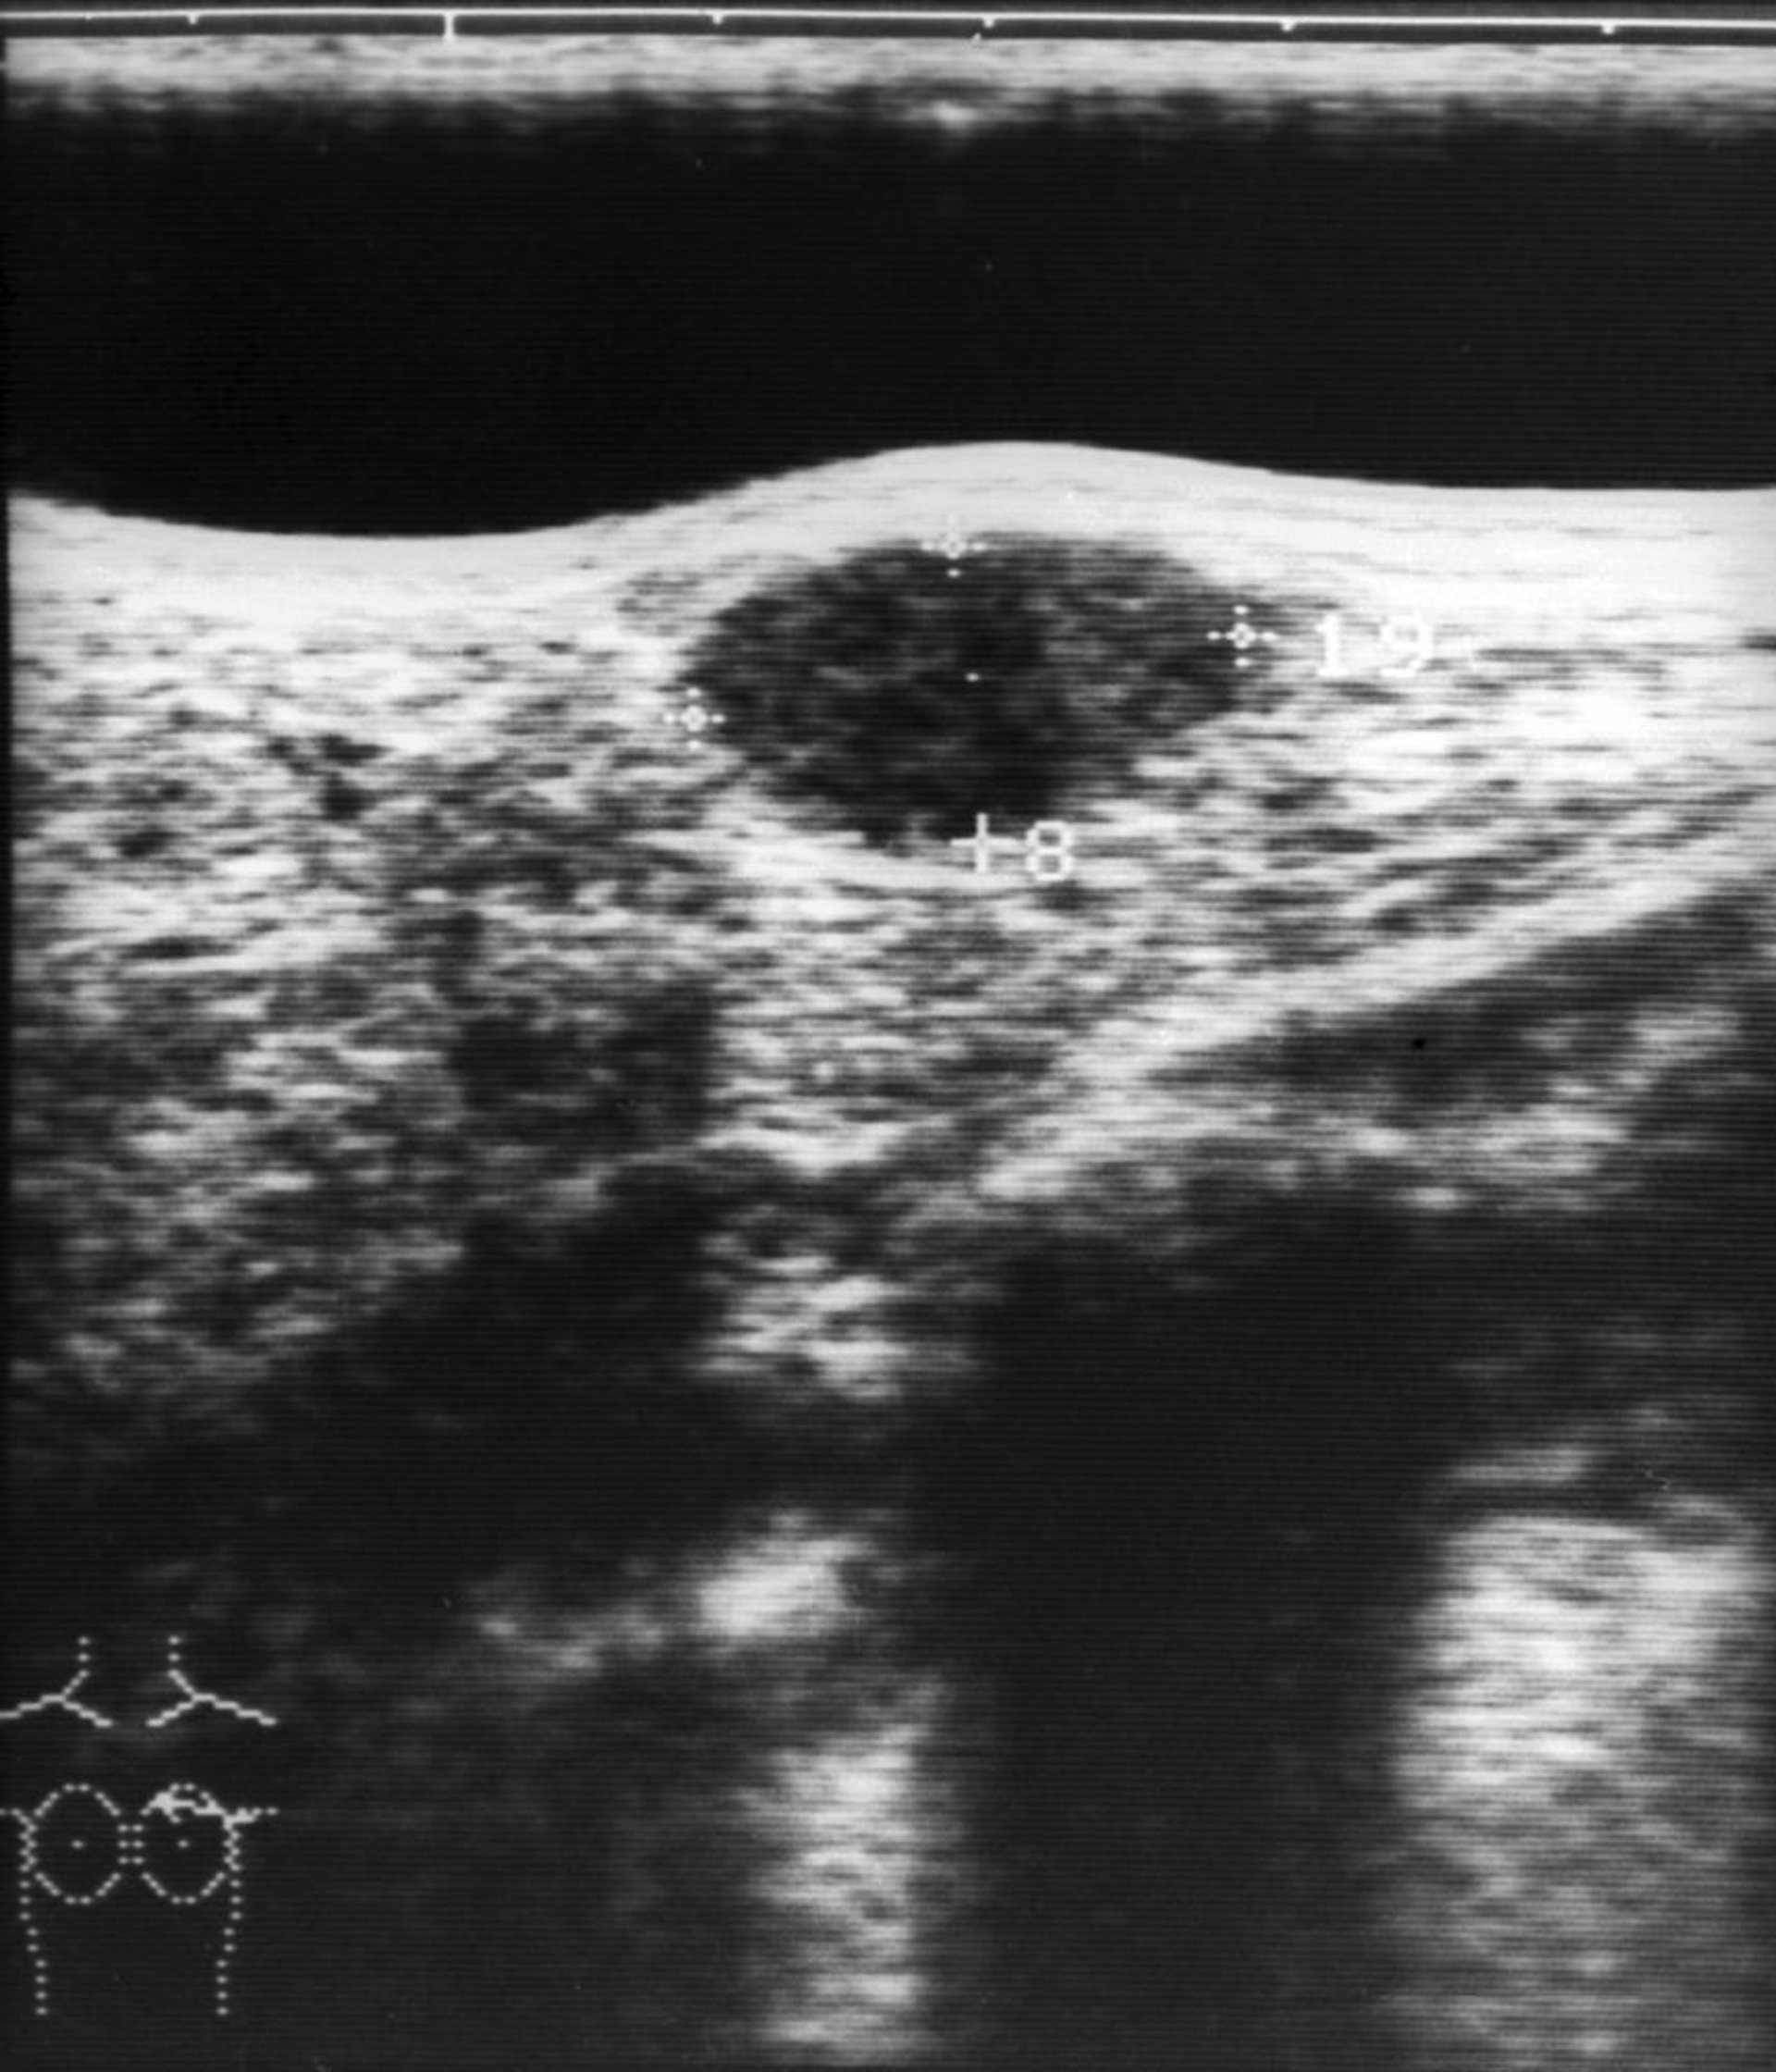

Hình ảnh này cho thấy siêu âm của một khối u tuyến xơ ở vú (cấu trúc giảm âm hình bầu dục ở trung tâm phía trên của hình ảnh).

ZEPHYR/THƯ VIỆN HÌNH ẢNH KHOA HỌC